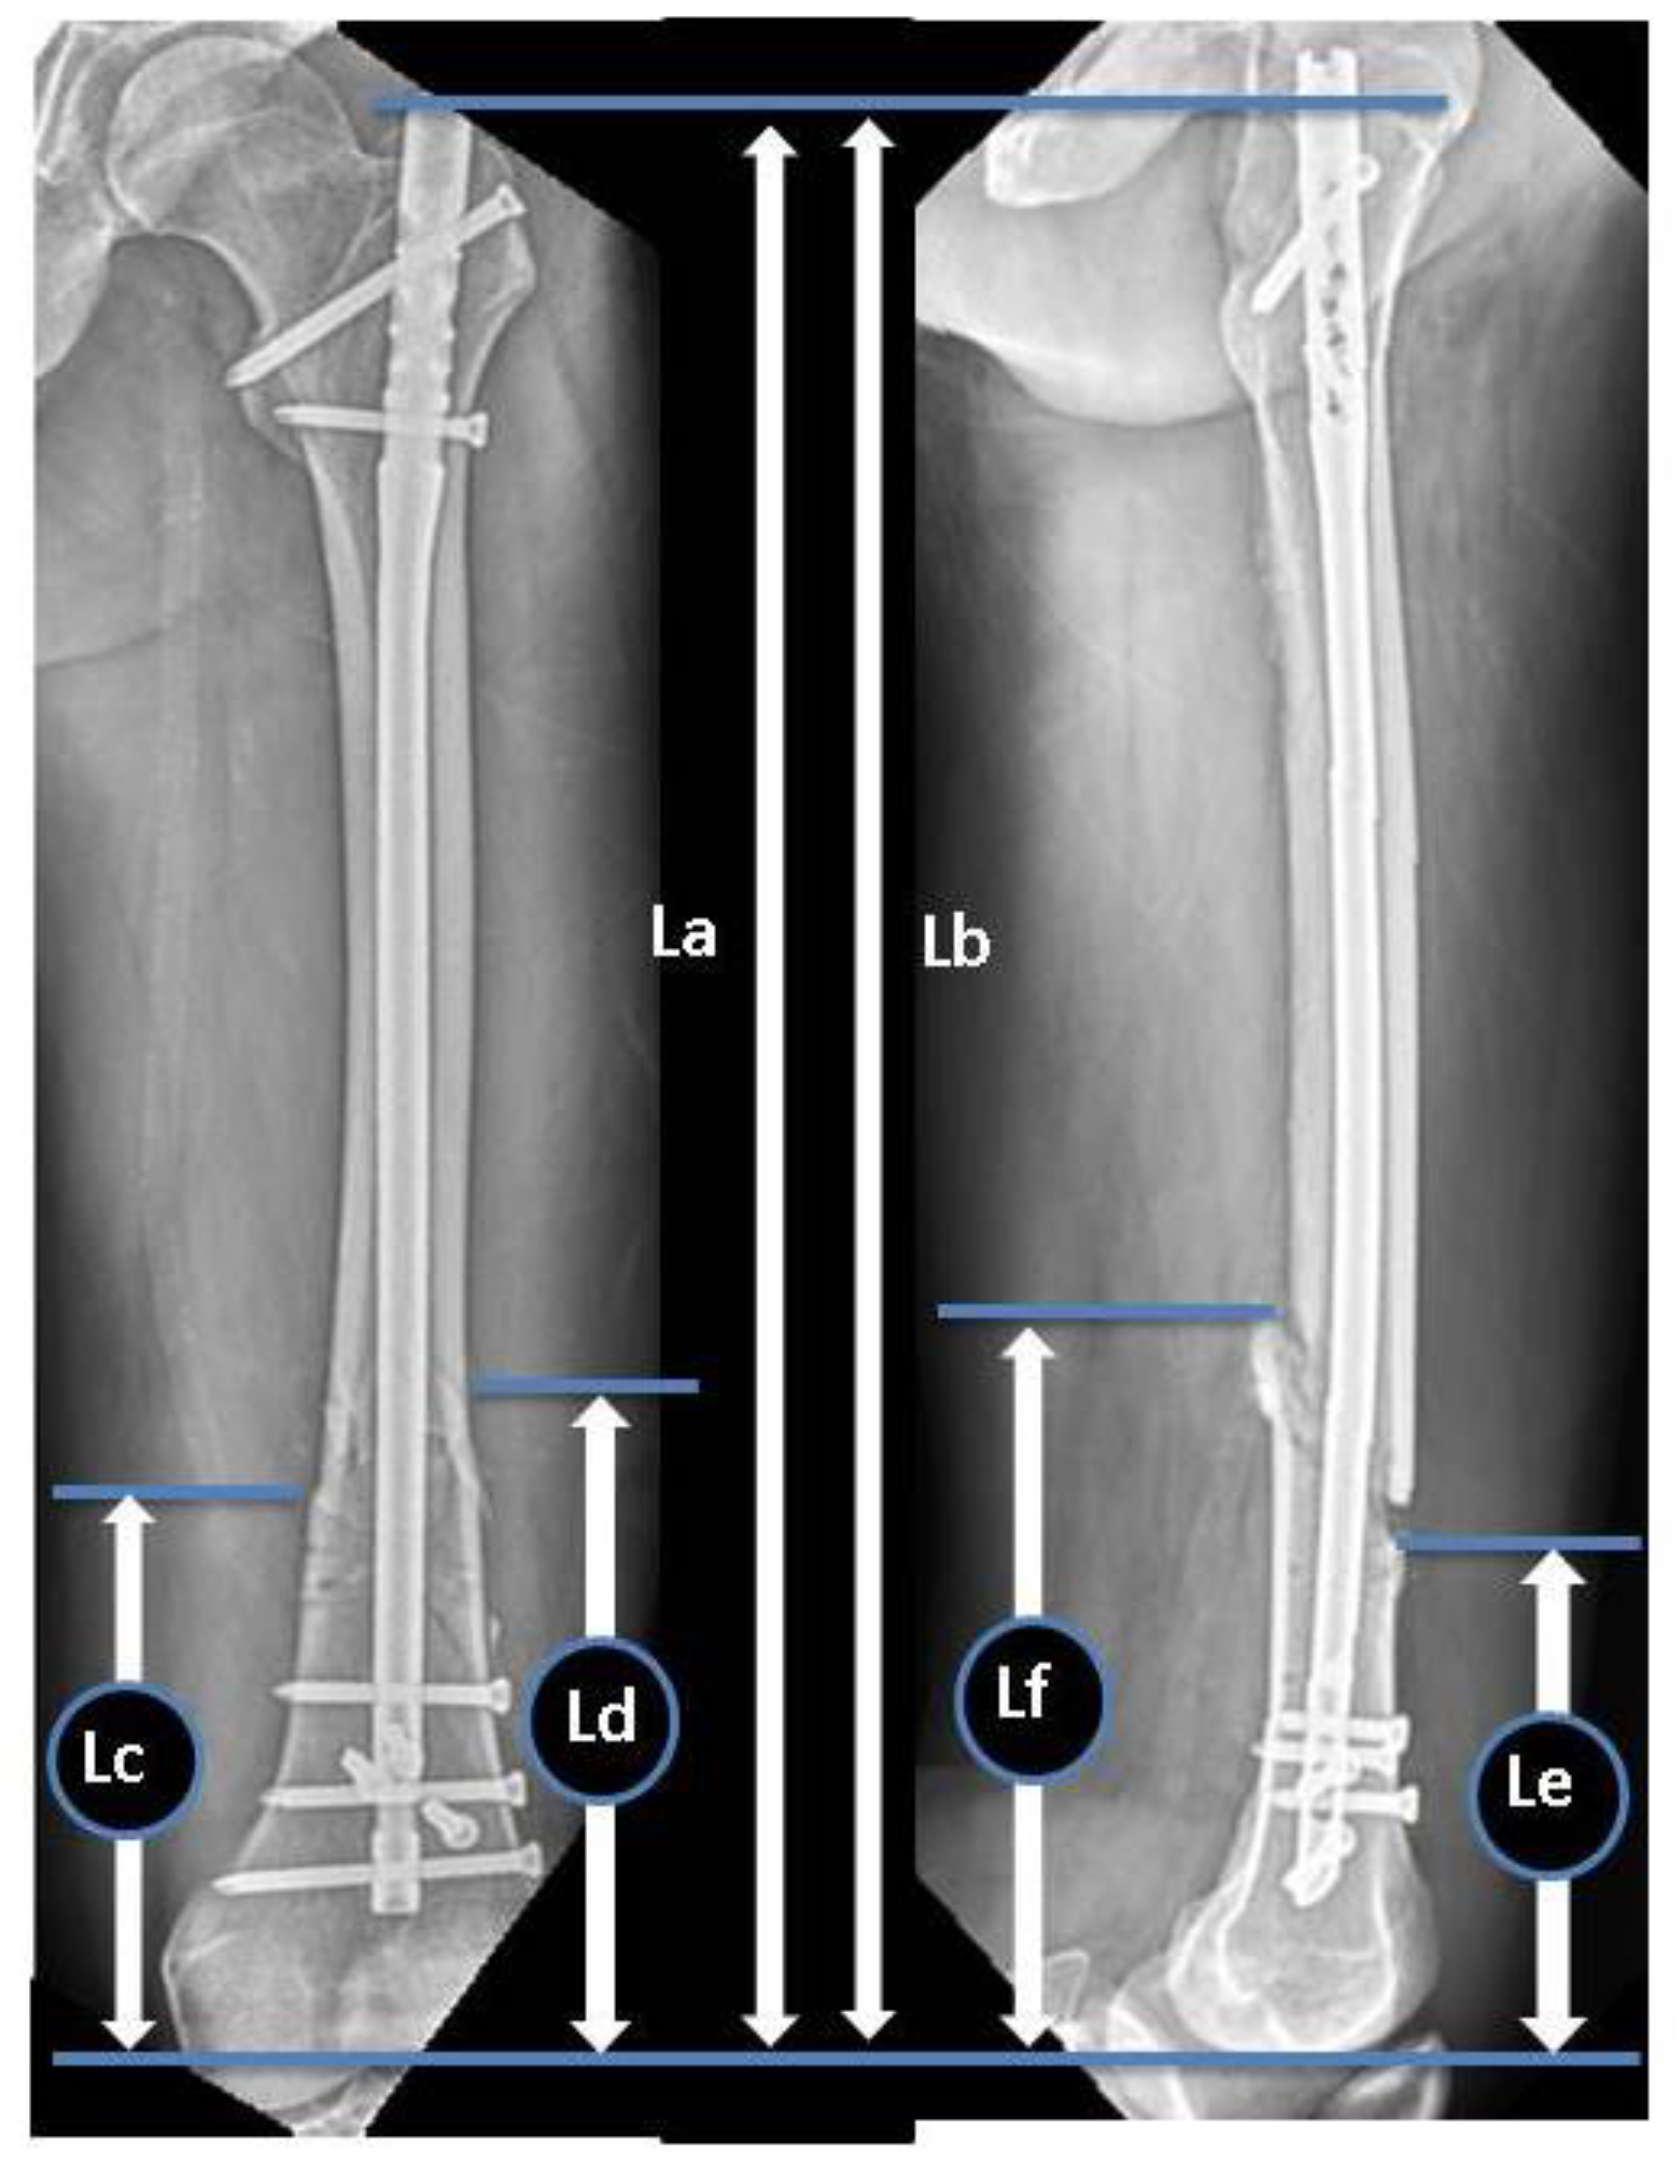

During the study period, eight parameters were measured in the anteroposterior (AP) and lateral views of preoperative and immediate postoperative radiographs to evaluate the radiographic risk factors for non-union. Preoperative radiographs were evaluated to classify the fracture types in accordance with the AO Foundation/Orthopaedic Trauma Association (AO/OTA) classification system [16]. Goniometric measurements were performed using immediate postoperative radiographs to determine the coronal plane angulation on AP radiographs and the sagittal plane angulation on lateral radiographs (the long axes of the proximal and distal fragment’s diaphyses intersect). The ratio of the distal fragment was measured using immediate postoperative radiographs in accordance with the protocol by Watanabe et al. (Figure 1). The ratio of the unfixed distal segment, as well as the ratio of IM canal diameter to nail size at the level of fracture (C/N ratio) (Figure 2), and the number of distal locking screws and poller screws were also measured.

Figure 1.

Ratio of the distal fragment: D/L, L: (La + Lb)/2, D: (Lc + Ld + Le + Lf)/4. D: Main distal fragment length, L: femur length, La: distance from the tip of the greater trochanter to the intercondylar notch in the AP view, Lb: distance from the tip of the greater trochanter to the intersection of the Blumensaat line and the trochlear groove line in the lateral view, Lc: distance from the intercondylar notch to the distal fracture line at the lateral site in the AP view, Ld: distance from the intercondylar notch to the distal fracture line at the medial site in the AP view, Le: distance from the intercondylar notch to the distal fracture line at the anterior site in the lateral view, Lf: distance from the intercondylar notch to the distal fracture line at the posterior site in the lateral view.